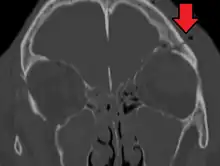

| Basilar skull fracture | |

| A subtle temporal bone fracture as seen on a CT scan | |